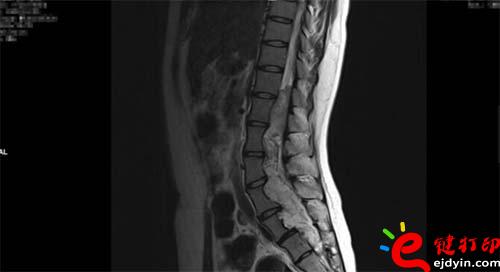

【VR和3D打印在微創(chuàng)椎管內(nèi)硬膜下先天性腫瘤切除術中的應用】近日,山西省人民醫(yī)院成功完成一例微創(chuàng)通道胸12-骶2椎管內(nèi)硬膜下先天性腫瘤切除術手術,在手術前醫(yī)院使用了西安鑫威泰科技自主研發(fā)的傲視虛擬現(xiàn)實數(shù)字醫(yī)療系統(tǒng)和3D打印模型進行手術規(guī)劃,制定手術方案,對本次手術的成功起到了至關重要的作用。